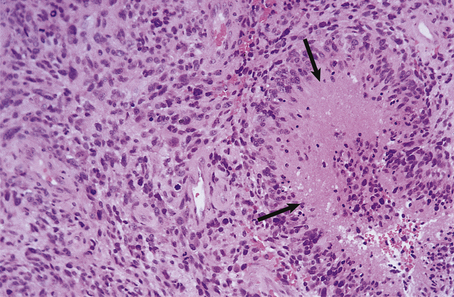

Abscess formation in the brain, as in other tissues, occurs when pus formation is accompanied by local tissue destruction (Fig. 26.14). A pyogenic membrane is formed, and the abscess develops a capsule composed of granulation tissue, and reactive astrocytes and their fibrillary processes. The adjacent brain is markedly oedematous, containing a perivascular inflammatory infiltrate of lymphocytes and plasma cells. Cerebral abscesses frequently enlarge and become multiloculate.

image

Fig. 26.14 Cerebral abscess: space-occupying lesion. A large abscess in the left parietal lobe is surrounded by oedematous white matter. This has acted as an expanding lesion and displaced the midline structures to the right. Death in this case resulted from a transtentorial brainstem herniation, with a characteristic haemorrhage in the central pons.

The clinical presentation is similar to that of acute bacterial meningitis, but focal neurological signs, epilepsy and fever are common manifestations. Abscesses act as space-occupying lesions and it is important to remember that a lumbar puncture must never be performed as an initial investigation on a patient with a suspected cerebral abscess (or other space-occupying lesion) as this may precipitate a fatal intracranial herniation. Antibiotic therapy is useful in the treatment of abscesses at an early stage, but once a capsule has formed surgical aspiration or excision is usually necessary. Complications of cerebral abscesses include:

meningitis

intracranial herniation

focal neurological deficit

epilepsy.